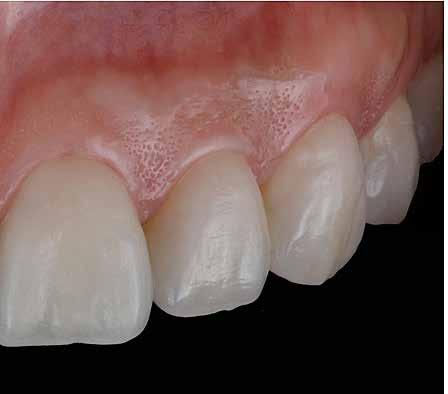

Az oxigén inhibíciós réteg kialakulásának elkerülése érdekében a kerámiafelszíneket glicerin géllel (Liquid Strip, Ivoclar Vivadent, Schaan, Liechtenstein) borítottuk, majd ezeket a felszíneket ismét 20-20 másodpercen keresztül világítottuk. A végeredmény megfelelt a páciens esztétikai igényeinek (6. a. ábra). Az átadott restaurátumok épségének megőrzése érdekében, a páciens számára éjszakai fogvédő sín készült. Az ötéves kontroll alkalmával megállapítottuk, hogy az elvégzett kezelésünk továbbra is sikeresnek tekinthető (6. b. ábra)

Az általunk alkalmazott adhezív rendszerek hatékonyságát nagymértékben növelhetjük azáltal, hogy a fogakat minimál invazív módon, azaz csak zománcon belül preparáljuk, és a kerámia héjakat kofferdám izolálásban ragasztjuk. Jelen esetismertetésünknek az volt a célja, hogy bemutassuk, hogyan lehet az adekvát módon kivitelezett kofferdám izolálással megelőzni

a munkaterület nyállal, vérrel vagy szulkusz-váladékkal történő kontaminációját. A megfelelő méretben kialakított perforációs nyílások és köztük lévő optimális távolság elengedhetetlen ahhoz, hogy a kofferdámot ideális módon tudjuk felhelyezni. Ezzel az esettel azt is bizonyítjuk, hogy a gumilepedő levegőfújással, fogselyemmel és teflonszalagok segítségével történő beforgatásával az ínyvérzés kialakulását el lehet kerülni. Ismételten szeretnénk hangsúlyozni, hogy a megfelelő kofferdám kapcsok használata nélkül nem tudtuk volna a preparált csonkszélt a gumilepedő szélétől eltartani. A kezelés során elért eredményeket jól alátámasztotta, hogy a páciens az ötéves kontroll vizsgálat során teljesen elégedett volt.